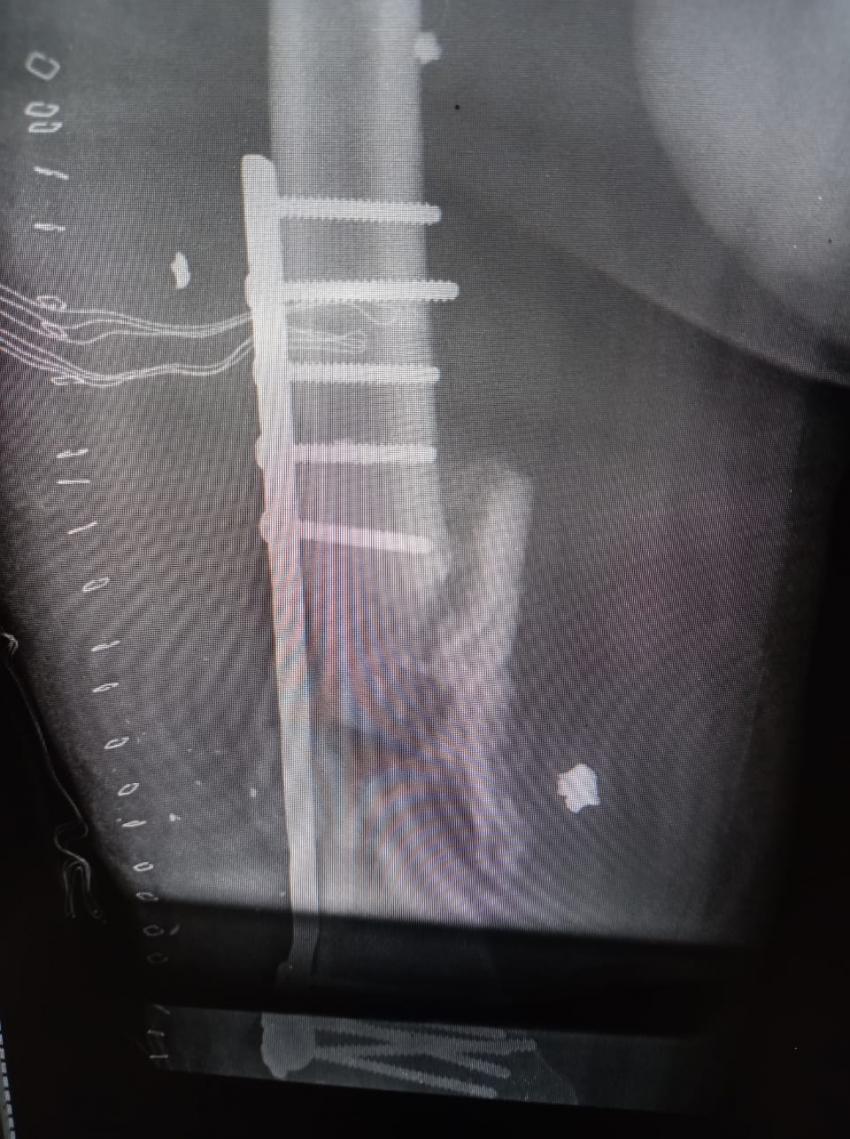

الراي نيوز - في إطار الجهود التي يقدمها المستشفى من أجل تقديم الخدمة والرعاية الطبية والإنسانية للأهل في قطاع غزة، أجرت طواقم المستشفى الميداني الأردني غزة /78 أمس السبت، عملية جراحية لتثبيت كسر مفتوح في أسفل عظم الفخذ (DISTAL FEMUR FX ORIF).

من جانبه بين طبيب جراحة العظام والمفاصل أن المريض كان يعاني من كسر مفتوح في أسفل عظم الفخذ اليمين مما أدى إلى تفتت العظم وتهتك الأنسجة المحيطة به نتيجة الإصابة التي تعرض لها المريض، وتم إجراء عملية جراحية وتركيب صفيحة معدنية وبراغي وإزالة المثبت الخارجي في المستشفى الميداني الأردني لكونه المستشفى الوحيد الذي ما زال مستمراً شمال القطاع.